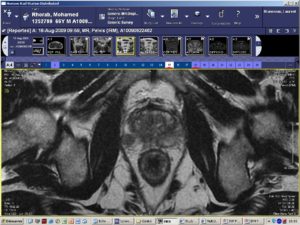

La surveillance active est une technique qui permet de surveiller le malade étroitement, lui évitant les effets indésirables de traitements, sans toutefois permettre une évolution non vue. Cela permet, grâce aux PSA, à l’IRM (photo 2), aux biopsies de la prostate répétées, de ne pas avoir les effets indésirables des traitements.

Photo 2 : IRM de la prostate